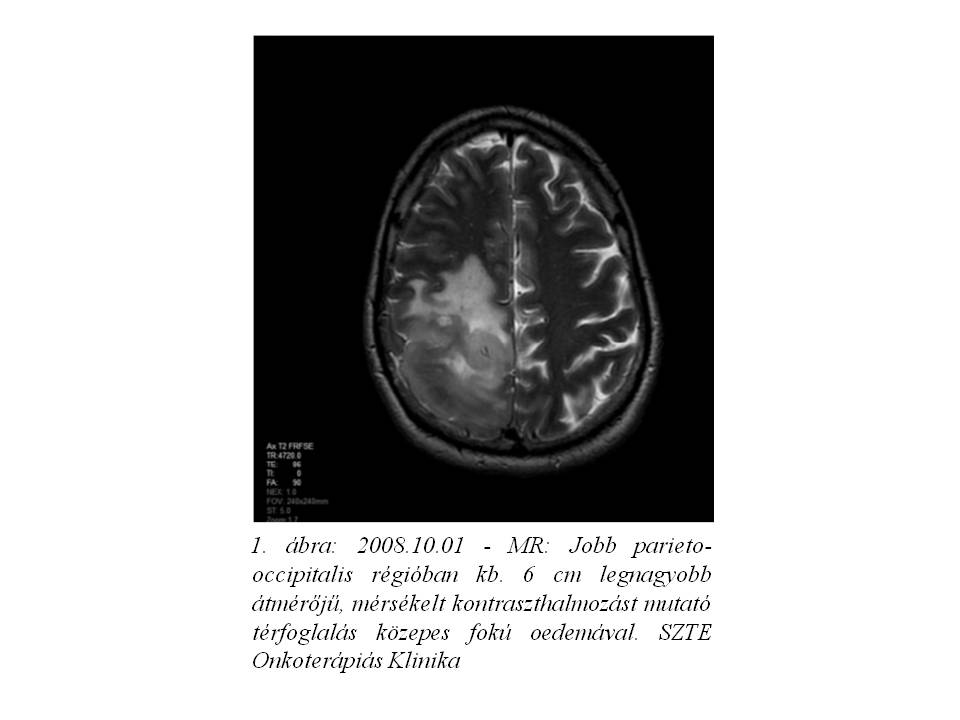

A 39 éves férfi betegnél 2004 nyarán jobb oldali parieto-occipitalis térfoglaló folyamatot detektáltak CT vizsgálattal, mely 2008 augusztusában növekedni kezdett (1. ábra). Az elvégzett biopszia grade II oligodendrogliomát igazolt. A beteg ezt követően definitív dózisú (22x1,8 Gy + 12x1,8 Gy) irradiációban részesült (2. ábra). 2 éven át fokozatos tumor regressziót, és stabil betegséget észleltünk, majd klinikailag stabil állapota mellett készült MR képalkotás 2010 júniusában tumor progressziót mutatott (3. ábra). Ekkor funkcionális MR és diffúzió súlyozott tractographia alapján neuronavigációs éber műtét során a makroszkópos tumor eltávolítása megtörtént. A hisztopatológia ekkor anaplasticus irányba transzformálódó, grade II-III oligodendrogliomát írt le. Posztoperatív 20x1,6 Gy dózisú reirradiáció történt, majd temozolomide monoterápia indult, mely 23 cikluson keresztül folytatódott (4. ábra). Ismételt tumor progresszió miatt 2012 szeptemberében betegünk reoperáción esett át, recidiváló, grade III-IV malignusan transzformálódó oligodendroglioma diagnózisával. A mozgásrehabilitáció mellett bevacizumab monoterápia indult egyedi méltányossággal, melyet 2013 júliusában kontroll MR által leírt subacut bevérzés miatt 4 ciklust követően a beteg kérésére felfüggesztettünk (5. ábra), 10 hónap viszonylagos jó állapot után gyors progresszió, majd 2014.06.27-én exitus következett be.